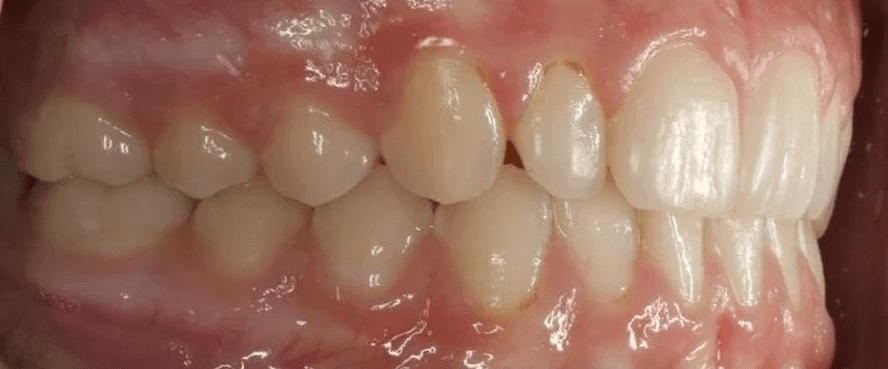

Initial treatment

INTRAORAL